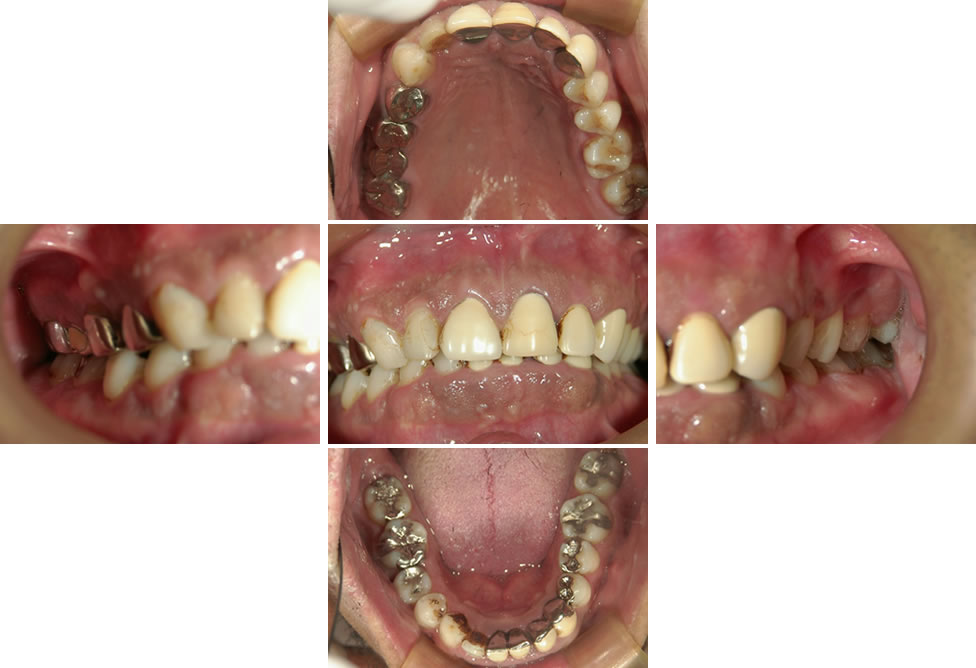

セラミック修復とインプラントによる全顎的な治療症例(50代:女性)

セラミック修復とインプラントによる全顎的な治療症例 ▼こちらの患者様は右上の前歯が折れたとのことで来院されました。 (図:初診時=正面・側方面・咬合面) 右下奥歯が欠損しており、義歯を作ったことがなく長期的に歯がない状態 […]